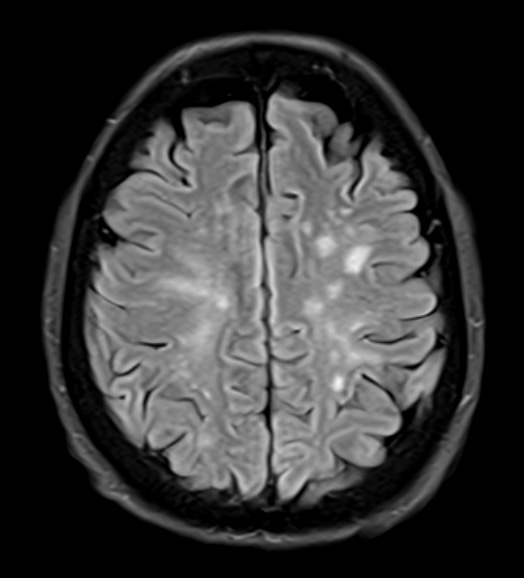

Case 17 History ---- The patient is a 56-year-old woman with a history of altered mental status and several areas of perivascular enhancement on imaging involving the centrum semiovale, pons, and basal ganglia. The clinical differential includes a vasculitic process and lymphoma. Operative Procedure: Open brain biopsy. ---- 17A1 Numerous hyperintense, largely white matter lesions are seen in this FLAIR MRI scan.